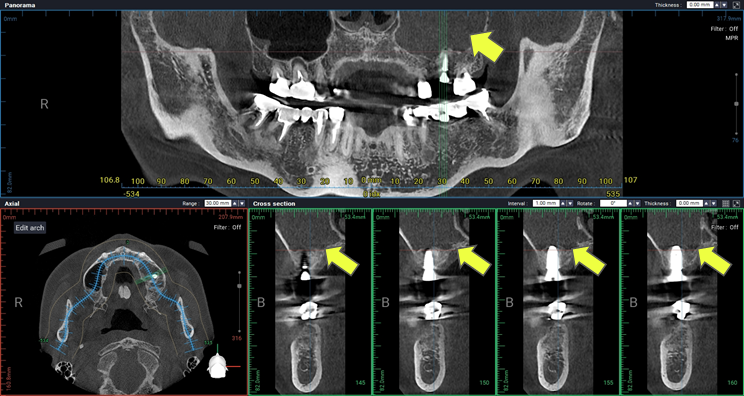

Radiographic Findings & Diagnosis

A panoramic radiograph revealed radiopacity within the left maxillary sinus. Clinical findings were consistent with implant-associated sinusitis at the #26 site.

Diagnosis: Implant-associated maxillary sinusitis

At the two-month follow-up, a panoramic radiograph and cone beam CT (CBCT) were obtained for comprehensive evaluation. Radiographic analysis showed that the prior radiopacity in the left maxillary sinus had resolved into radiolucency, suggesting resolution of the inflammation and restoration of sinus health.